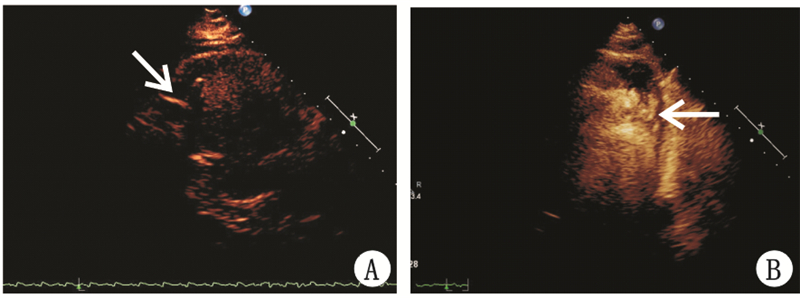

经胸超声心动图监测3例患者中2例伞叶足位于左心尖,指引导管和心脏长轴一致。1例伞叶足靠近左室下壁中下段(图 1A),在经胸超声心动图直视下进行及时调整后指引导管和心脏长轴保持一致(图 1B)。术中猪尾导管造影及超声心动图监测均提示封堵器位置固定良好。2例左心声学造影于左室显影即刻未发现室壁瘤内造影剂信号(图 2A),彩色多普勒检查未探及伞周血流;1例左心声学造影于左室显影即刻室壁瘤内可见少许造影剂信号(图 2B),彩色多普勒检查探及伞周少许残余血流信号(图 3A)。3例彩色多普勒检查Parachute伞叶均可见快闪伪像(图 3B)。

| A:未见伞周漏(箭头示伞周未发现造影剂信号);B:轻度伞周漏(箭头示伞周少许造影剂信号) 图 2 Parachute伞植入后左心声学造影 |